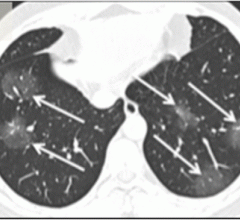

February 5, 2020 — In a special report published in the journal Radiology, researchers describe computed tomography (CT) ...

February 4, 2020 — Since January 2020, the Coronavirus (2019-nCoV) outbreak at Wuhan, China, has attracted a great deal ...

January 31, 2020 — One of the first imaging studies on the coronavirus (2019-nCoV) was published online today as ...